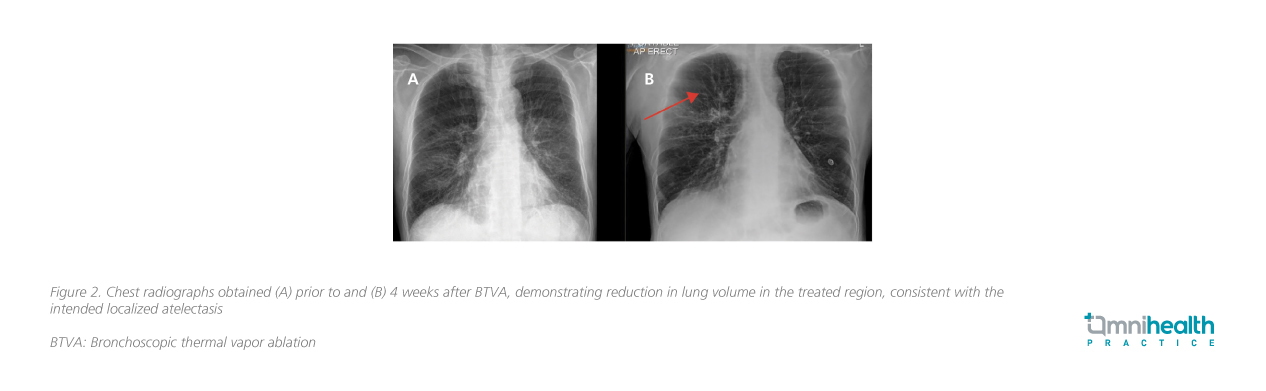

The patient subsequently underwent BTVA under spontaneous general anesthesia. Treatment was targeted to the RB1 (activation time: 5.4 seconds) and RB3 (activation time: 6.8 seconds) segments of the right upper lobe. The procedure was well tolerated without complications. A chest radiograph on postoperative day 1 showed a reduction in right upper lobe volume. Clinically, the patient reported improved exercise tolerance during the early recovery period.

At the 4-week follow-up, the patient reported symptomatic improvement and no longer required supplemental oxygen, maintaining an SpO2 of 98% on room air. The SGRQ score improved by 10 points, reflecting a meaningful enhancement in QoL. Pulmonary function testing and the 6MWT remained stable at this early stage, with further physiological changes anticipated as the treatment effect continues to evolve. A follow-up chest radiograph also demonstrated a visible reduction in lung volume in the treated region (figure 2).